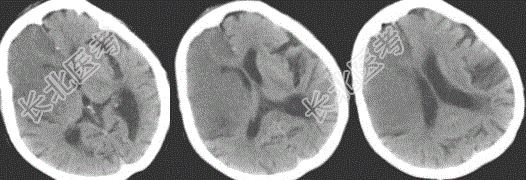

- 多项选择题2.患者检查图像如下,应考虑何种疾病

- 多项选择题3.诊断依据是哪些

A、昏迷,大小便失禁12小时

B、CT显示右侧大脑额、颞叶大片状均匀低密度灶

C、既往高血压病史

D、右侧侧脑室受压

E、大脑镰钙化

F、左侧基底节区低密度灶

- 多项选择题4.大面积脑梗死的典型表现包括

A、梗死区域与该区动脉供血区域一致,呈扇形或楔形,同时累及灰质和白质

B、梗死发生6小时后,可见大脑中动脉水平段条形高密度影,外囊与岛叶皮质界限模糊

C、梗死区脑沟变浅

D、6~24小时部分病灶出现低密度

E、大部分病例24小时之后才出现典型的低密度改变